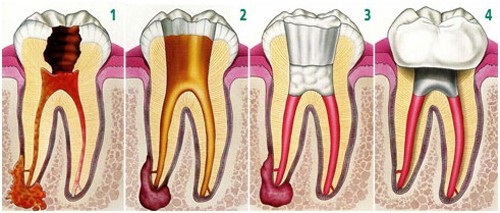

Cấu tạo của răng sứ bao gồm 2 phần cơ bản, phần sườn bên trong có thể bằng hợp chất kim loại, titan, sứ và được phủ bên ngoài một lớp sứ để gần giống với răng thật. Tùy thuộc vào vật liệu làm ra răng sứ mà chúng ta có thể chia thành 2 loại là răng sứ kim loại và răng sứ không kim loại.

– Để bọc mão hay cầu răng thì cần phải mài răng thật nhỏ lại, thông thường sẽ mài hết phần men răng. Độ bền chắc lâu dài của răng sứ sau này sẽ phụ thuộc vào kỹ thuật mài răng của bác sĩ, mài ít quá cũng không được, nhiều quá cũng không được, phải theo một tỷ lệ nhất định. Việc mài quá nhiều sẽ gây kích thích tủy răng, ảnh hưởng đến việc sử dụng răng sau này – đối với răng sống, còn những răng đã lấy tủy nếu mài nhiều quá sẽ làm cùi răng dễ bị gãy. Trường hợp mài răng ít quá sẽ làm cho răng trông rất thô, dễ bị cộm, gây ảnh hưởng đến cách ăn uống hàng ngày.

– Những răng sống, không chữa tủy mà được bọc răng toàn sứ thì răng sẽ có độ bền giống như răng thật. Nếu bọc răng kim loại sẽ tùy thuộc vào khung sườn của răng, răng kim loại thường sẽ sử dụng hơn 3 năm, răng sứ Titan sử dụng trên 5 năm.

– Những răng chữa tủy thì độ bền của răng sứ sẽ phụ thuộc theo thời gian sử dụng. Bởi do tủy răng đã không còn, răng của bạn sẽ rất giòn và dễ gãy. Ngoài ra, độ bền của răng sứ còn phụ thuộc vào cách chăm sóc và vệ sinh hàng ngày của bệnh nhân, không nên ăn nhai những đồ cứng để đảm bảo thời gian sử dụng được kéo dài.